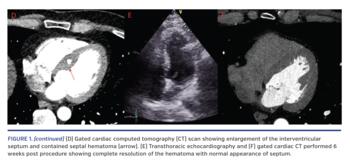

A 43-year-old male underwent CTO-PCI of the right coronary artery (RCA) for stable angina (Figure 1A). Antegrade wire escalation and dissection/re-entry techniques failed, so a retrograde strategy was adopted. A 0.014˝ Fielder FC guidewire (Asahi Intecc) was advanced into the second septal perforator and exchanged via a Corsair microcatheter (Asahi Intecc) for a Sion wire (Asahi Intecc), which was advanced to the distal RCA. Attempts to advance the Corsair microcatheter, a Caravel microcatheter (Vascular Perspectives), and a 1.2 x 10 mm Mini-trek balloon (Abbott Vascular) into the distal RCA were unsuccessful due to distal tortuosity, and subsequent angiography showed evidence of a septal perforation. The patient was hemodynamically stable and the procedure was abandoned.

Transthoracic echocardiography immediately post procedure demonstrated an echo-free space in the septum with no evidence of intracardiac shunting consistent with a septal hematoma (Figures 1B and 1C). This was confirmed on gated computed tomography scanning (Figure 1D). Electrocardiogram showed no evidence of cardiac conduction delay and the patient remained stable and was discharged the following day. Repeat echocardiography and cardiac computed tomography performed 6 weeks later showed complete resolution of the hematoma (Figures 1E and 1F).